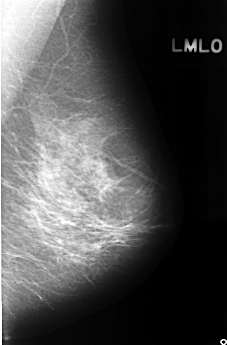

C_0338_1.LEFT_MLO

LEFT_MLO LINES 4480 PIXELS_PER_LINE 2944 BITS_PER_PIXEL 12 RESOLUTION 50 NON_OVERLAY